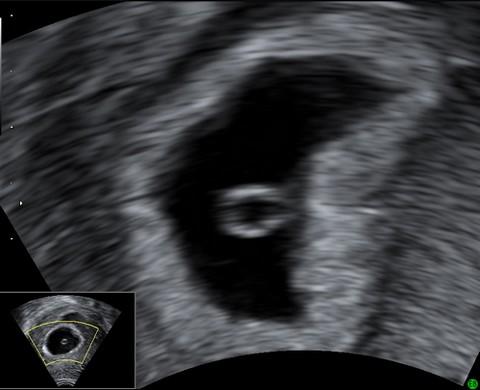

5. týden těhotenství je možno graviditu ověřit pomocí ultrazvukového vyšetření – prokáže se přítomnost zárodku v děloze. Srdeční akce plodu lze prokázat na ultrazvuku až o 1-2 týdny později.

Ultrazvukový snímek pochází z ukončeného 5. týdne (5+0). Je na něm vidět žloutkový váček o velikosti 5 mm.